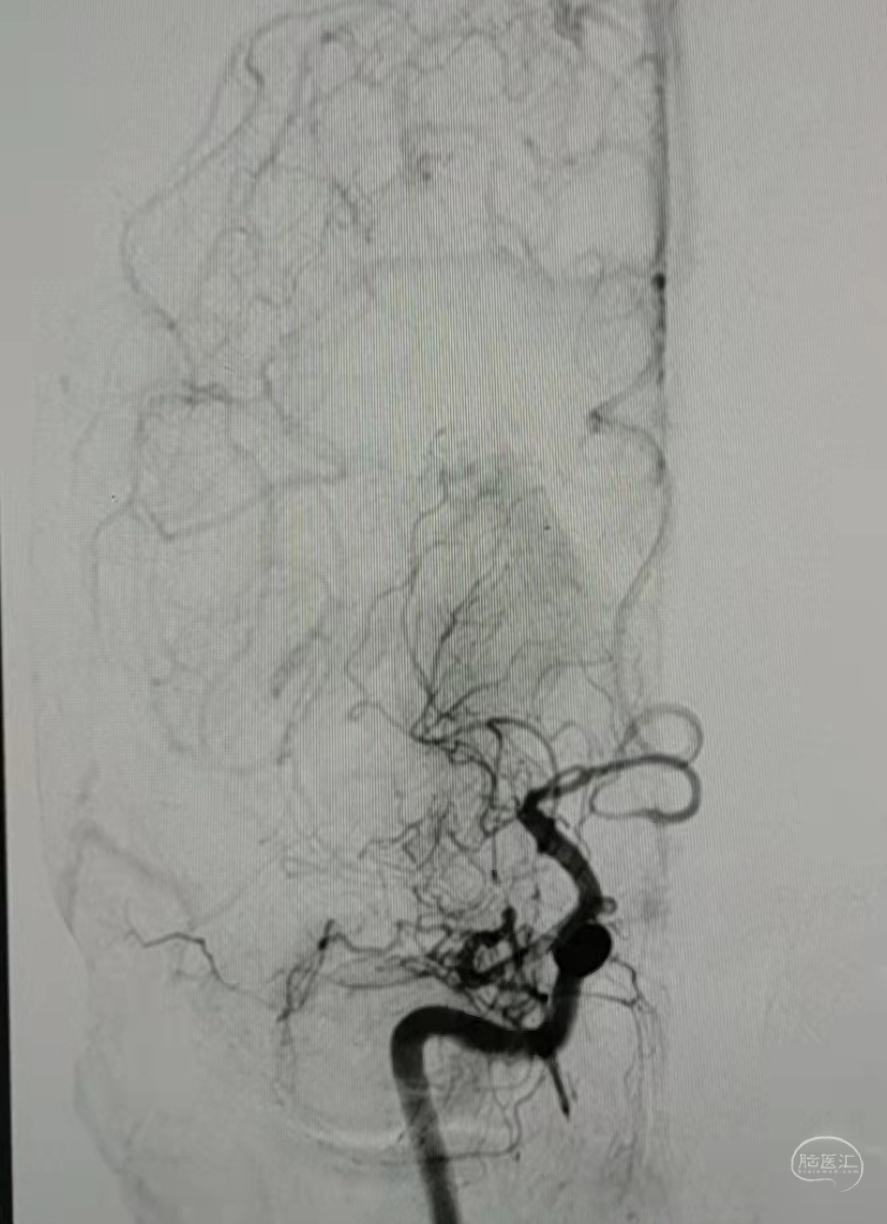

DSA:右侧大脑中动脉、大脑前动脉闭塞,烟雾样血管形成。

DSA:左侧大脑中动脉、大脑前动脉闭塞,烟雾样血管形成。

DSA:右侧大脑中动脉、大脑前动脉闭塞,烟雾样血管形成。

DSA:左侧大脑中动脉、大脑前动脉闭塞,烟雾样血管形成。